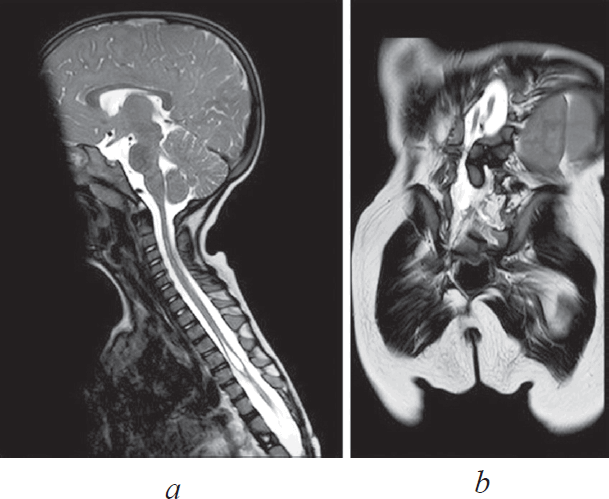

По данным магнитно-резонансной томографии имеют место гидромиелическая киста на уровне Th5-Th6, расщепление спинного мозга на два гемикорда ниже уровня Th7 (рис. 2). Прямых данных за компрессию спинного мозга нет. Деформация обладает значительным потенциалом прогрессии за счет поперечного дефекта передних структур. Первоочередной задачей хирургического лечения в настоящей ситуации является стабилизация позвоночника с дальнейшим рассмотрением вопроса о мобилизации и/или декомпрессии спинного мозга. Инструментальная фиксация не представляется возможной, так как на уровне порока отсутствуют пригодные к установке опорных элементов металлоконструкции как передние, так и задние структуры. Единственным применимым вариантом стабилизации является передний спондилодез без фиксации металлоконструкцией. Учитывая обусловленный отсутствием ригидной внутренней фиксации высокий риск несостоятельности костного блока, предпочтительно использование пластического материала, обладающего оптимальными прочностными, остеокондуктивными, остеоиндуктивными и остеогенными характеристиками. Принято решение выполнить спондилодез аутогенным реберным трансплантатом в сочетании с композитным материалом, состоящим из сульфата кальция (остеокондуктивная среда), деминерализованного костного матрикса (остеоиндуктивная среда) и аутогенного пунктата костного мозга (остеогенная среда).

Рис. 2. Предоперационная магнитно-резонансная томография: a — гидромиелическая киста на уровне Th5-Th6; b — расщепление спинного мозга на два гемикорда ниже уровня Th7